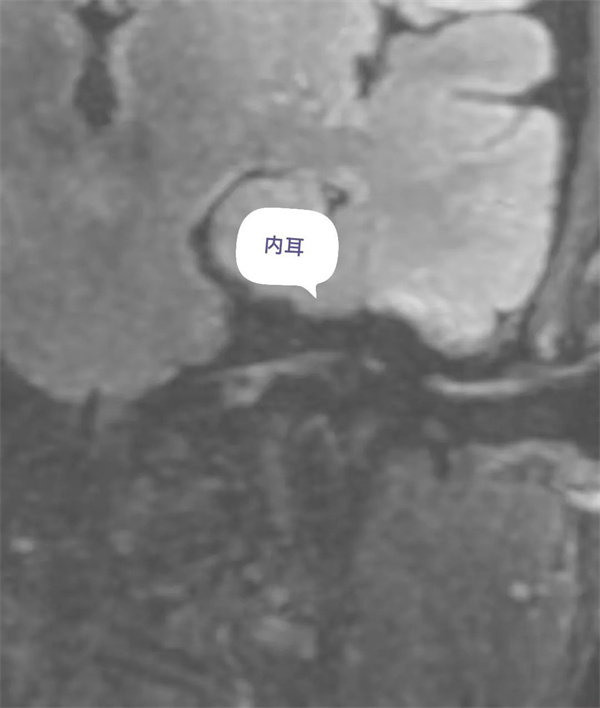

圖11:增強前磁共振內(nèi)耳圖。

圖12:增強后內(nèi)耳外淋巴液磁共振顯示圖。